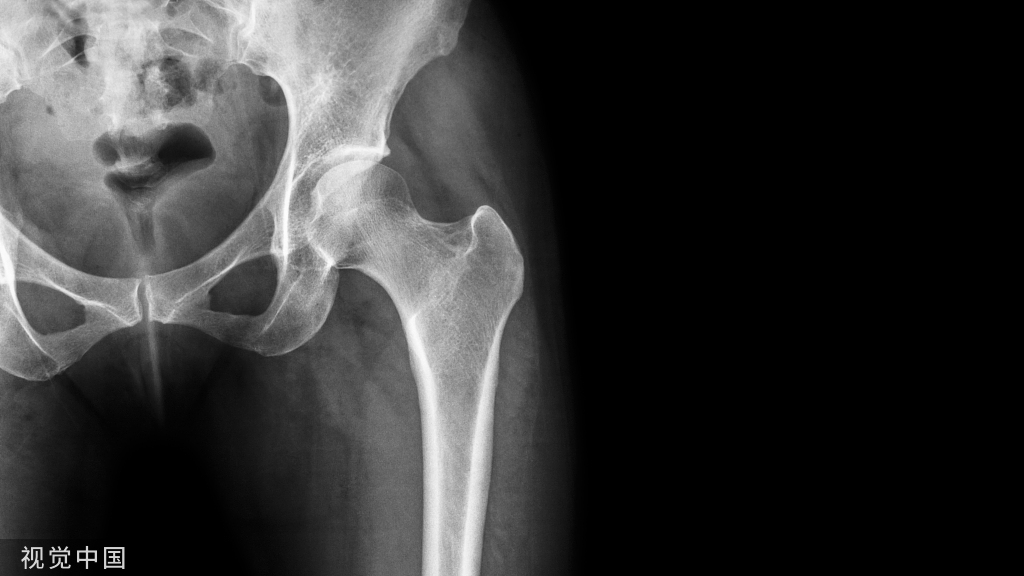

下胫腓螺钉固定既往作为治疗下胫腓联合损伤金标准(如下图),但存在螺钉松 动断裂、复位不良等并发症。